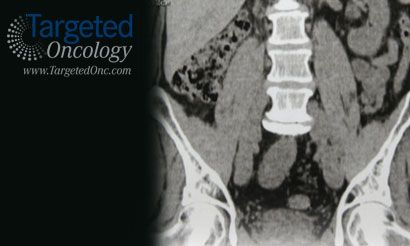

Unresectable Hepatocellular Carcinoma